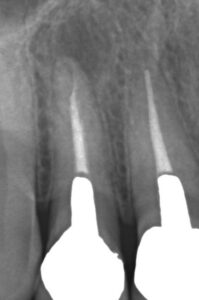

【6年後】

【左右ともに根尖病巣が治癒 骨が再生】

【右上2番 治療前】【右上2番 治療後】

【左上2番 治療前】【左上2番 治療後】

治療その後 治療から6年経過するが再発することなく順調に経過 そもそも抜髄時にきちんと治療が行われていればこのような根尖病巣は生じなかったと思われる。もちろん抜髄は理論的には根管の解剖学的形態を考えれば100%の成功はないわけだが、それを言い始めればすべての処置、手術等で100%の成功があるかと言われればそんなわけはない。ただし保険だから出来ないというのも言い訳だと考える。保険だと出来ないというドクターは自費でも出来ない。機械や薬剤が最新であれば必ず治るというわけではない。普段まずい料理を提供しているシェフが、お金を出すから明日世界一の料理を作ってくれと言われても出来ないのと同じである。普段から保険で適当な治療をしているドクターがお金を出すからと言って治せるかといったら治せない。普段からきちんとした仕事をしていていざというときにも対処できるのがプロではないだろうか。